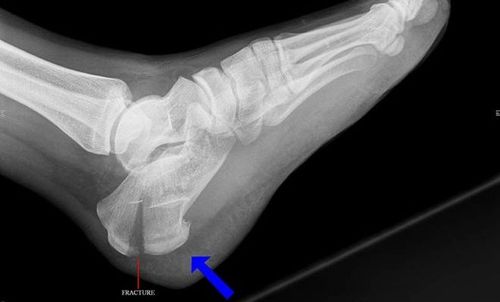

Врачи отмечают, что перелом пяточной кости часто сопровождается сильной болью в области пятки, отеком и затруднением при ходьбе. Основными признаками являются также синяки и изменение формы стопы. При подозрении на перелом важно обратиться к специалисту для проведения рентгенографического исследования, которое поможет подтвердить диагноз и определить степень повреждения.

Перелом пяточной кости лечит травматолог. Специалист осматривает повреждение и назначает рентгенографию, а при необходимости — компьютерную томографию. Затем он решает, нужно ли хирургическое вмешательство или можно обойтись консервативным методом лечения.